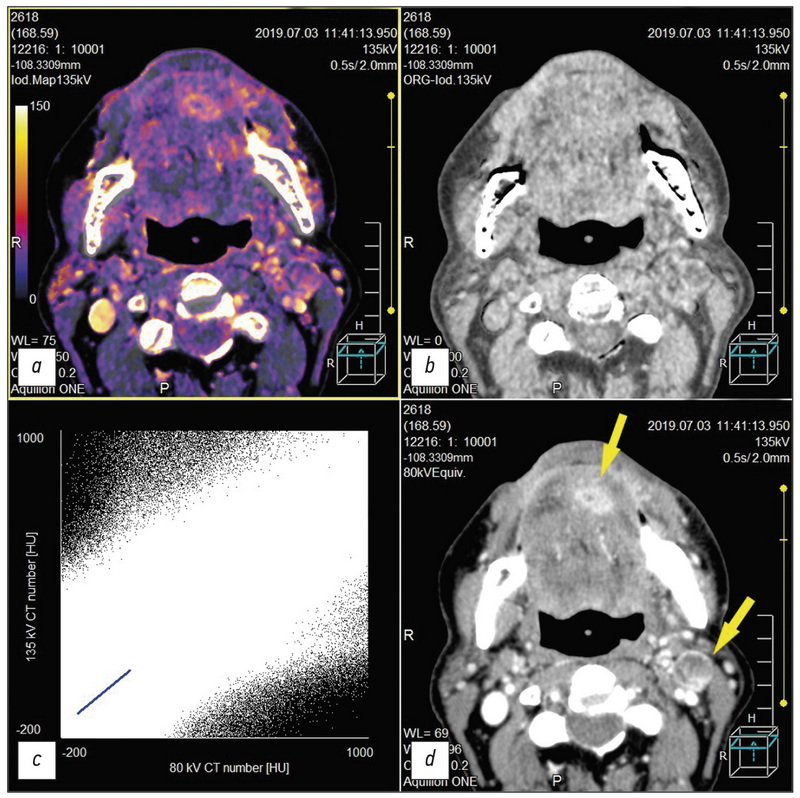

对使用双能计算机断层扫描 (DECT) 诊断头颈癌的出版物进行了审查; 研究了通过 DECT 方法获得的数据的定性和定量分析结果,并在该定位的肿瘤中进行了静脉对比增强; 显示了构建碘图以获得额外诊断信息的重要性; 描述了在牙种植体伪影的背景下改善口咽区域可视化的方面。 文章中介绍的许多科学作品强调了当前的技术水平和“原始数据”DECT 后处理的作用,获得了一系列头颈部肿瘤和其他病理变化的单色图像,包括将 DECT 与静脉造影增强和常规计算机断层扫描在减少患者辐射负荷方面进行比较,特别是由于在后处理期间从 DECT 体积的对比系列中获取虚拟原生诊断图像。 除了最新的相关科学数据外,该评论还包括对 DECT 作为一种方法的发展历史的著作的参考。 简要概述了 DECT 的物理原理和该方法的发展前景。